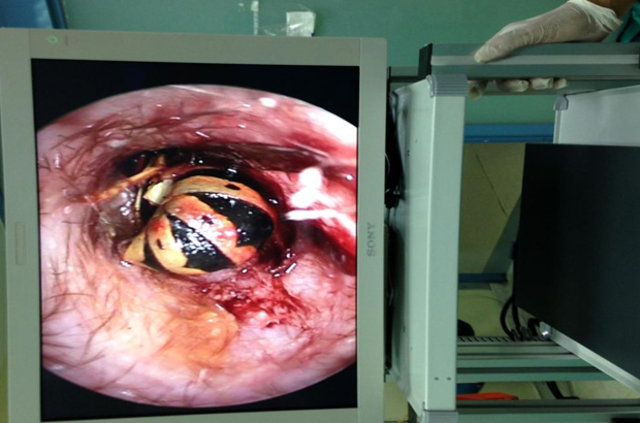

Serik İlçesi Devlet Hastanesi'nde yaşandı. Kulak ağrısı şikayeti ile hastanenin Kulak Burun Boğaz (KBB) polikliniğine giden 64 yaşındaki Fatma Türker'in yapılan muayenesinde, kulak zarına yakın bir bölgeye kene yapıştığı tespit edildi. KBB Uzmanı Op. Dr. Mustafa Altıntaş, kulak içerisinde sık karşılaşmadıkları keneyi görünce büyük şaşkınlık yaşadıklarını söyledi.

Serik'te hayvancılık ve çiftçilikle uğraşan hastanın 2- 3 gün önce özel bir sağlık kuruluşuna kulak ağrısı şikayeti ile başvurduğunu söyleyen Op. Dr. Altıntaş, "Gittiği doktor, kulağında iltihap olduğunu söylemiş. Kendisine ilaç vererek evine göndermiş. Tabi hastanın şikayetleri geçmeyince bu kez bize geldi. Yaptığımız muayenede kenenin kulak içine yapıştığını ve hala canlı olduğunu gördük. Özel bir teknikle kenenin tam ağzını yakalayarak, kulaktan çıkardık. Bölgede keneden kalma herhangi bir parça kalmamasına özellikle dikkat ettik" diye konuştu.